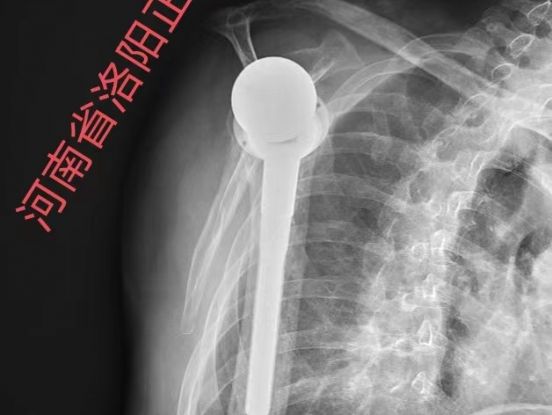

• REGENETEN 治疗高龄巨大肩袖撕裂

宁凡友

河南省洛阳正骨医院(河南省骨科医院)